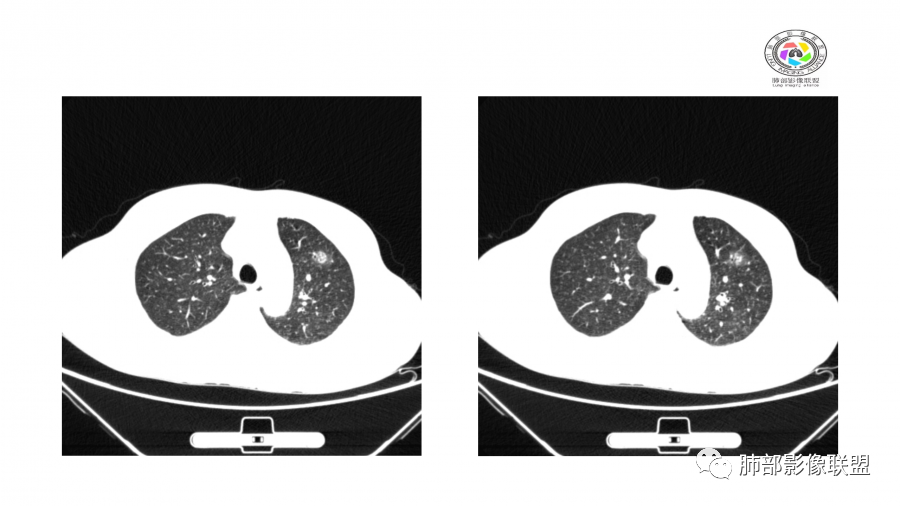

南边:

边界模糊,距离胸膜有间隙,内部支气管通畅

一月后:

病灶此起彼伏